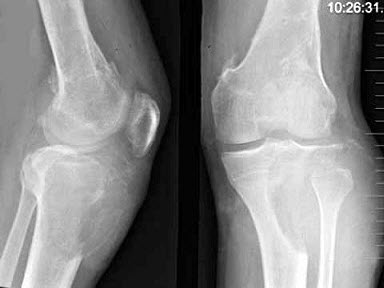

115、单项选择题

男,22岁,左侧膝部肿胀,疼痛2月余,结合影像学检查,最可能的诊断是()

A.骨脓肿

B.骨肉瘤

C.骨髓炎

D.动脉瘤样骨囊肿

E.软骨肉瘤

116、名词解释 狭颈征